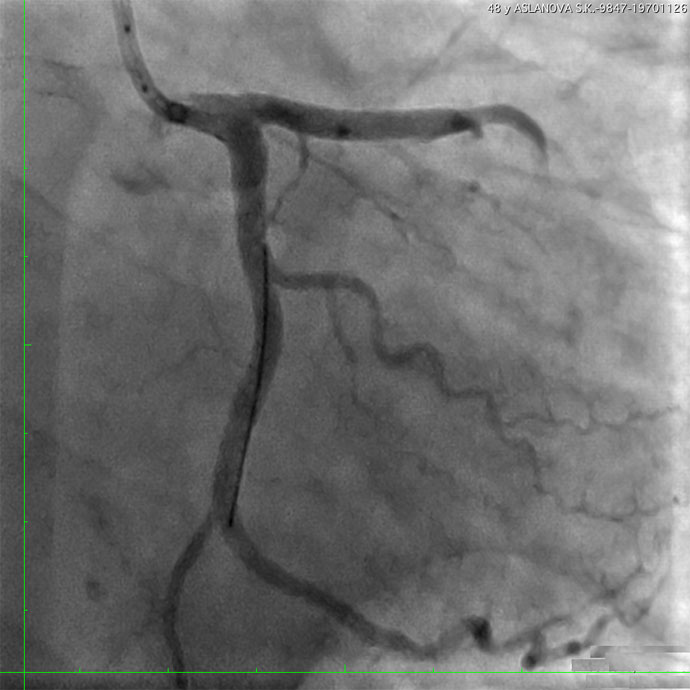

В рентгеноперационной по результатам КАГ выявлен критический стеноз (сужение) ствола левой коронарной артерии и устья правой коронарной артерии — иными словами, практически отсутствовало кровоснабжение большого объема сердечной мышцы. Во время попытки реваскуляризации (восстановления кровотока) правой коронарной артерии у больной произошла остановка сердечной деятельности. Несмотря на проведение расширенного комплекса реанимационных мероприятий, сердечная деятельность не восстановилась, в связи с чем по жизненным показаниям для экстракорпорального поддержания жизни принято решение о применении механической поддержки кровообращения методом экстракорпоральной мембранной оксигенации (ЭКМО). Была проведена имплантация системы бивентрикулярного обхода желудочков сердца (Cardiohelp)) для протезирования сердечной функции. Аппарат ЭКМО выполнял функцию искусственного сердца и позволил прекратить непрямой массаж, несмотря на отсутствие сокращений миокарда. На фоне процедуры вено-артериальной ЭКМО выполнена баллонная ангиопластика со стентированием коронарных артерий.

— У больной выявлено сочетание поражение двух основных артерий сердца. Реваскуляризация миокарда у таких пациентов сопряжена с высоким риском развития фатальных осложнений. У нашей пациентки произошла рефрактерная (устойчивая к терапии) остановка кровообращения. Реанимационные мероприятия продолжались больше 20 минут, пока специалисты центра ЭКМО устанавливали систему экстракорпорального поддержания жизни. Система ЭКМО обеспечивала ток крови, минуя сердце, и насыщение ее кислородом, на этом фоне было выполнено стентирование устья правой коронарной артерии — установлено 2 стента, и ствола левой коронарной артерии — 1 стент, в результате кровоток по обеим артериям был восстановлен.